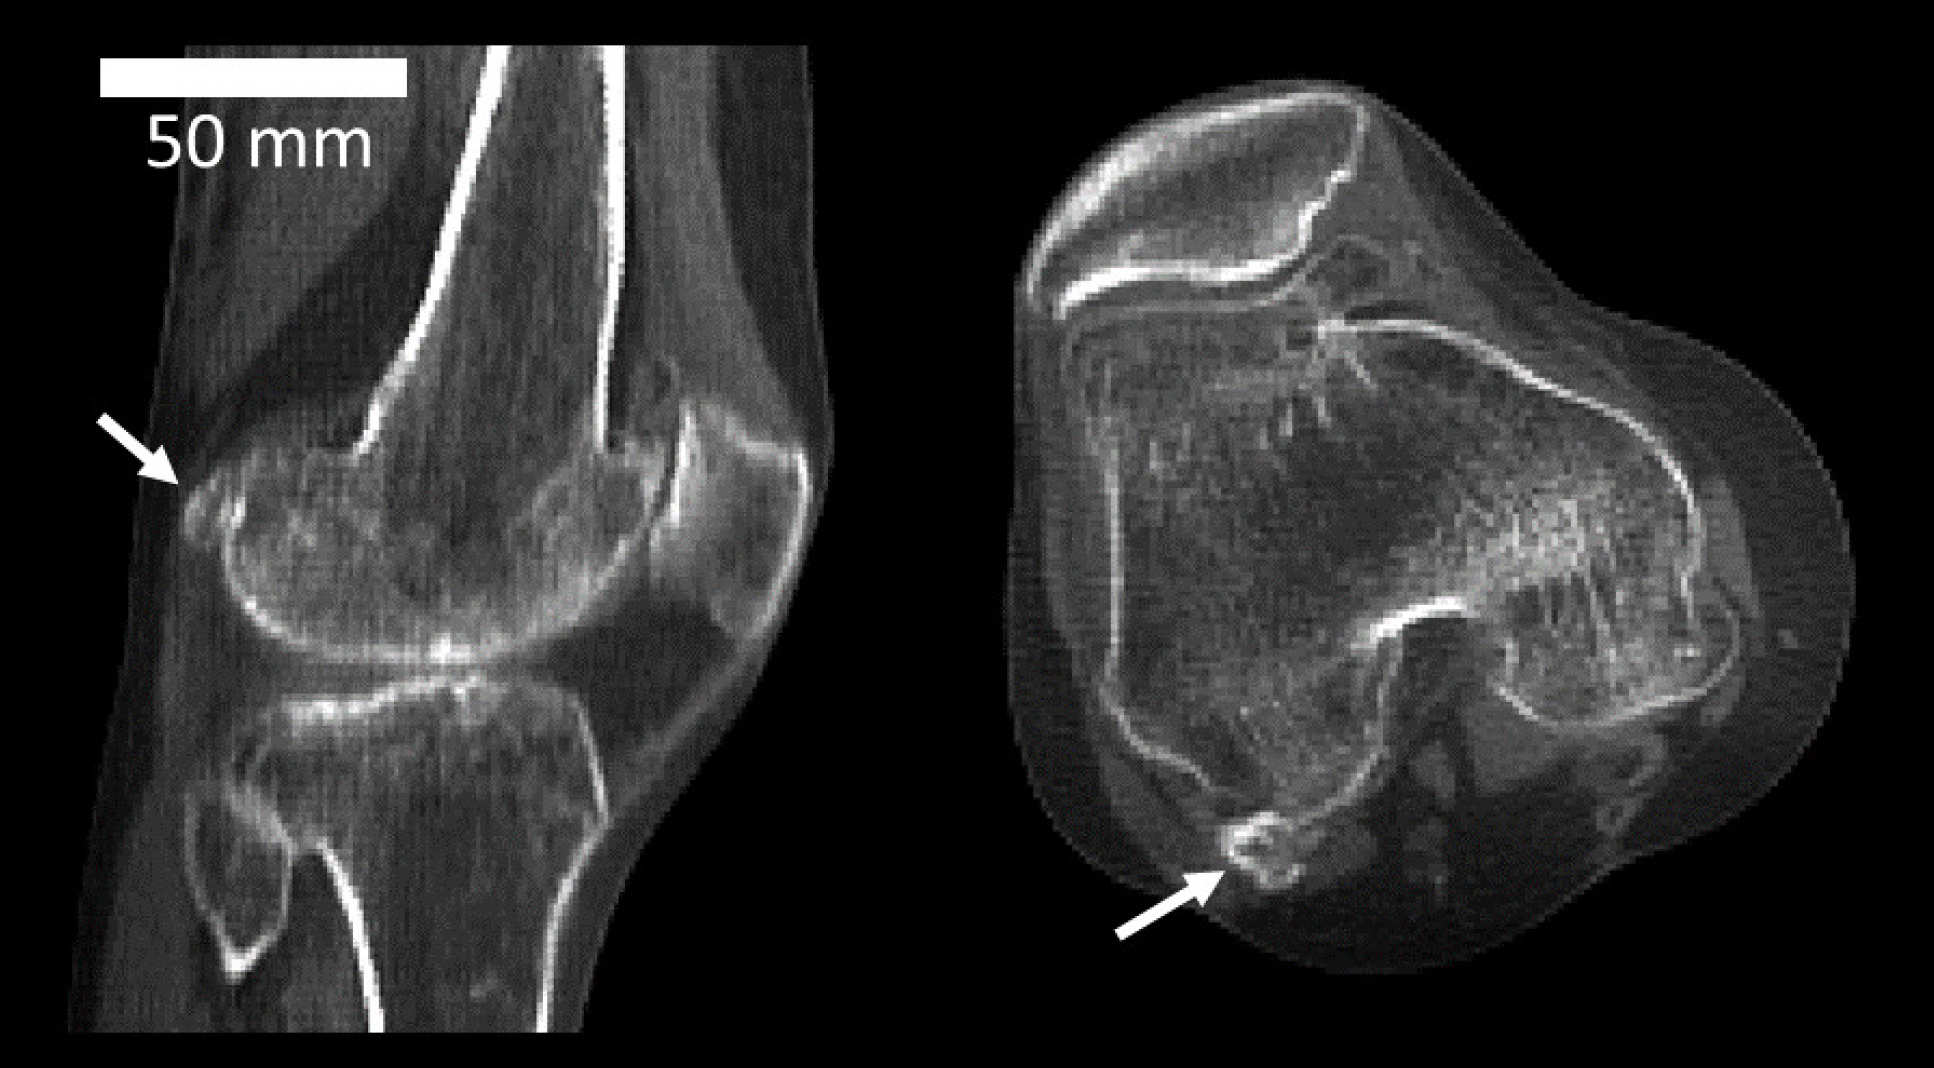

10. Mystery arthritis-linked knee bone three times more common than 100 years ago | Imperial News

Is it time to adjust the official number of bones in the human body? In April, Imperial researchers found that the small fabella bone, once thought to be a relic of the past, has made a comeback over the last century. The mystery bone, growing in a tendon of a muscle behind the knee, is now present in 39 per cent of the world population, making it three times more common compared to 100 years ago.

Interestingly, researchers are not sure about the function of the fabella, but their analysis shows that people with osteoarthritis of the knee are twice as likely to have it.